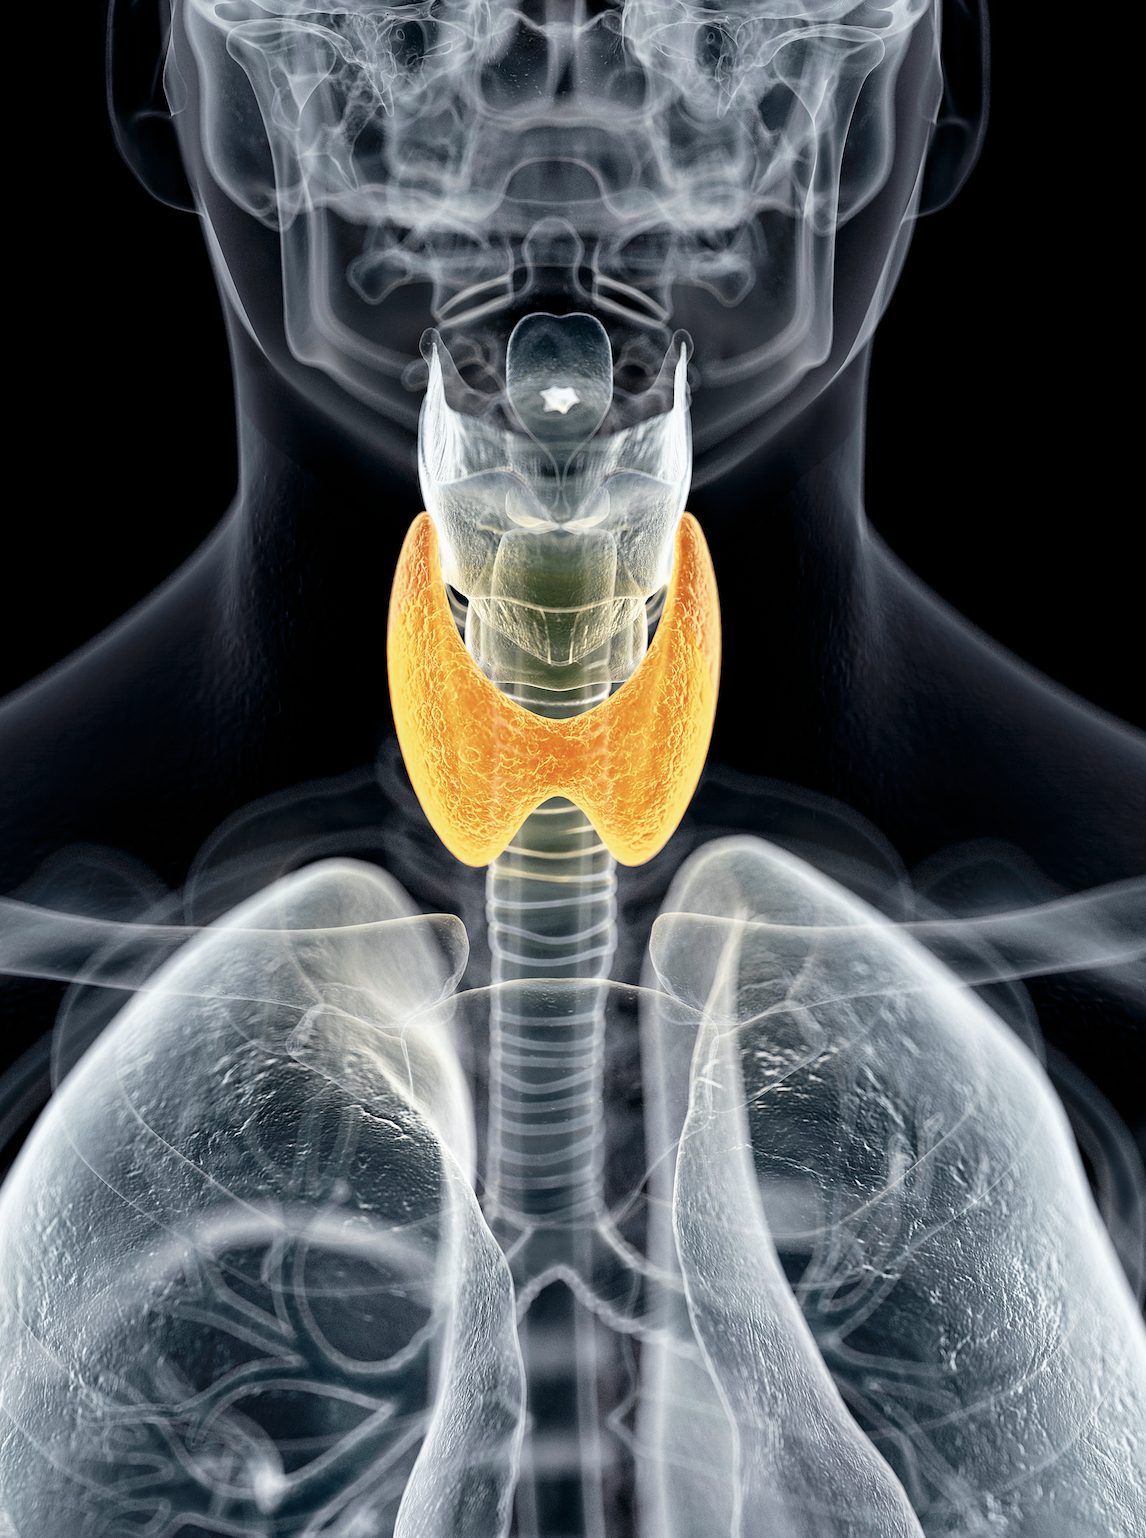

Esta pequeña glándula con forma de mariposa es el centro de control del metabolismo, su director de orquesta. Su función es sintetizar, almacenar y liberar hormonas tiroideas, que son las encargadas de asegurar que los tejidos y órganos de nuestro cuerpo funcionan correctamente y a la velocidad adecuada. «Regulan casi todas las funciones: cardiaca, muscular, hepática…; por eso, una mala salud tiroidea va a condicionar síntomas de todo tipo», afirma la doctora Elena Navarro, especialista en Endocrinología y Nutrición en el Hospital Universitario Virgen del Rocío, de Sevilla, y coordinadora del Área de Tiroides de la Sociedad Española de Endocrinología y Nutrición (SEEN).

Pese a su papel crucial, la glándula permaneció inadvertida durante siglos. Sería Thomas Waterton (1614-1673) quien le diera su nombre –por su proximidad al cartílago tiroides–, aunque ha habido que esperar hasta el siglo XXI para que se generalice la sensación de que existe una 'epidemia' de disfunciones tiroideas.